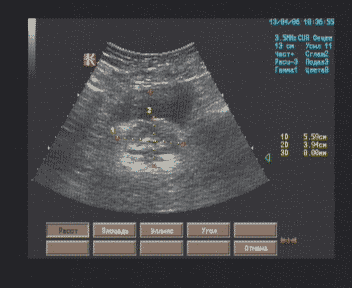

При подозрении у больного на врожденный порок сердца специалист эхокардиографии должен четко придерживаться определенного плана обследования. В противном случае можно не разобраться с пороком или описать только часть порока. Помимо В-режима в исследовании этой категории больных большую роль играет цветовой и непрерывноволновой допплер. Цветовой допплер, или ЦДК, позволяет быстро диагностировать патологический кровоток в сердце и в сосудах сердца. Особую ценность он представляет для диагностики шунтов. Непрерывноволновой допплер позволяет рассчитать максимальное систолическое давление в легочной артерии, оценить степень стенозов, степень и значимость клапанной регургитации. Исследование у больного с врожденным пороком сердца может продолжаться дольше, чем у больного с другой патологией сердца, поскольку доктору часто приходится долго выводить оптимальные эхокардиографические позиции для диагностики того или иного порока и сканировать кровоток в поисках шунтов буквально по кадрам. Все это может занять много времени.

При подозрении на врожденный порок сердца очень важно установить анатомическое положение камер сердца, т.е. морфологически левого и правого предсердий и морфологически левого и правого желудочков. Помимо этого необходимо определить их функциональное состояние (артериальное или венозное). Отхождение сосудов от камер сердца и впадение их в камеру сердца играет важную роль в оценке порока.